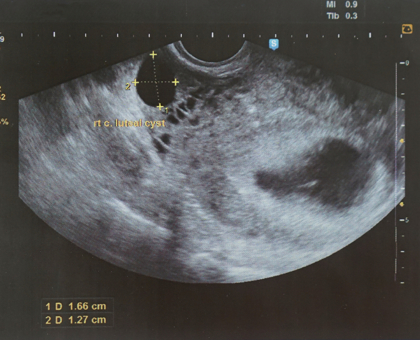

Semaine d’aménorrhée : 7ème

Semaine de grossesse : 5ème

Embryon : 6 mm

Lors de cette cinquième semaine, il est temps de faire la prise de sang pour vérifier le taux hormonal, et ainsi pouvoir officiellement dater votre grossesse. Vous en profiterez également pour vérifier si vous êtes bien immunisée contre la toxoplasmose et la rubéole. Enfin, si vous allez chez un gynécologue équipe d’un appareil d’échographie, vous aurez la chance d’entendre clairement les battements du cœur de votre bébé !